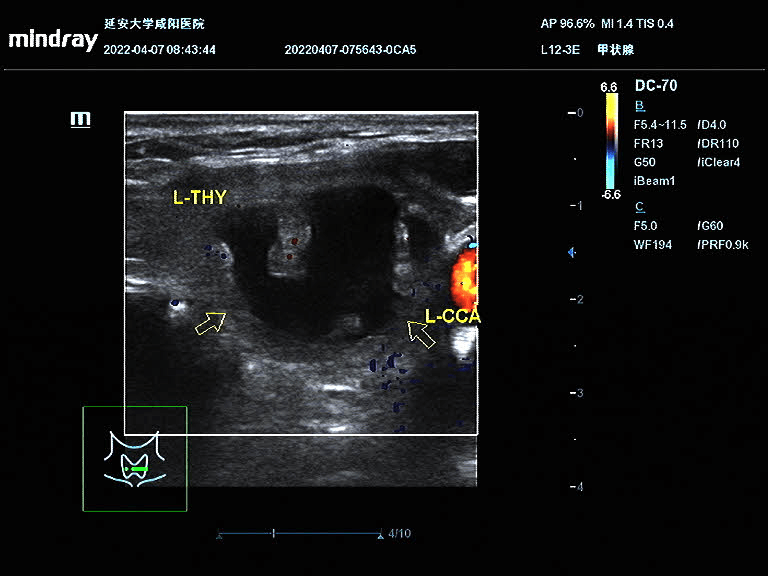

王女士在半年前因颈部包块就诊于我院,超声提示甲状腺左叶囊实性包块,因疫情原因未进一步治疗;近半年来包块明显增大,颈部膨隆,为进一步治疗就诊于我院血液内分泌科。彩超诊断为甲状腺左侧叶囊实性结节,患者因惧怕疼痛,不愿手术,选择保守治疗;后得知甲状腺结节可以超声引导下微创治疗,遂联系超声科进行咨询;超声科医生对王女士的甲状腺结节进行评估后,就射频消融术的优点、术前的准备、术中的风险、术后的注意事项详细讲解,王女士当即决定选择射频消融术治疗甲状腺结节。4月9日下午在介入超声手术室顺利完成手术,术后颈部仅一个针眼大小。术中囊性部分抽吸为黑红色粘稠液,实性部分消融治疗,术后即刻造影结节内未见造影剂回声。

术前结节大小:44.9mm×31.8mm×22.2mm

对结节的囊性部分进行穿刺抽吸+聚桂醇反复冲洗